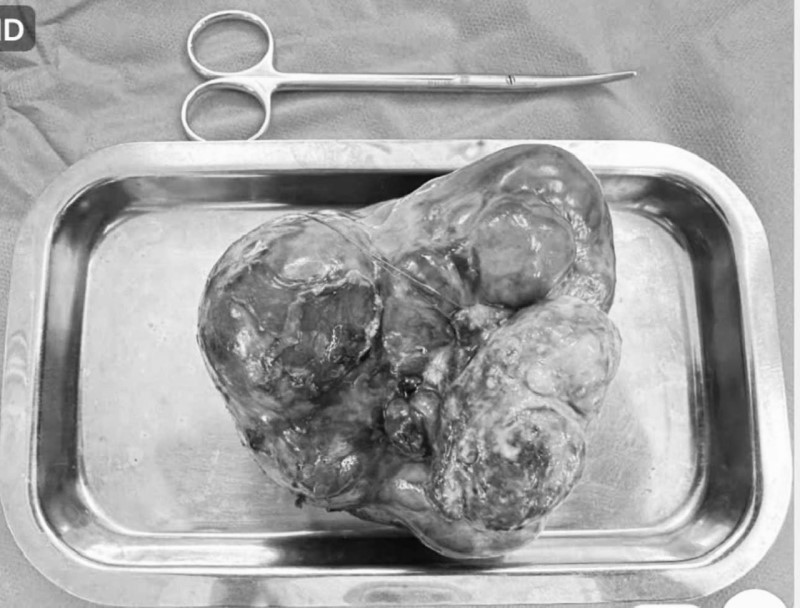

“Qua ghi nhận, khối u có kích thước lớn chiếm gần như trọn ổ bụng. Khối u dính vào dạ dày, một phần nằm trọn trong lòng dạ dày. Ekip phẫu thuật tiến hành cắt bỏ 1 phần dạ dày chứa u và bóc tách toàn bộ u, đưa ra ngoài cơ thể bé. Khối u nặng khoảng 1.000 gram. Sau khi lấy u ra, các bác sĩ tiến hành khâu tạo hình lại dạ dày cho bé. Sau mổ, tổng trạng bé dần cải thiện, vết mổ khô và đã bắt đầu bú sữa”, Ths.BS Hồ Văn Anh Dũng thông tin.